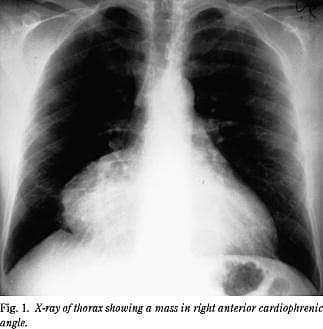

En 38-årig mand, der var rask fraset catarrhalia to uger tidligere, blev indlagt på et lokalsygehus efter et døgns højresidige skuldersmerter og senere respirationssynkrone smerter retrosternalt. Objektivt fandtes der let halsvenestase med patienten i siddende stilling samt pulsus paradoxus, men i øvrigt var han ikke hæmodynamisk eller respiratorisk påvirket. Temperaturen var 37,5 °C. CRP var 57 mg/l, og leukocyttallet var 16,9 × 109 /l. Øvrige værdier inklusive koronarenzymer var inden for normalområdet. Et ekg viste sinusrytme uden tegn på iskæmi eller pericarditis. Et røntgen af thorax viste en stor, rund struktur langs højre hjerterand. Strukturen målte ca. 10 cm i diameter (Fig. 1 ). En transtorakal ekkokardiografi (TTE) afslørede en cysteagtig homogen proces langs højre atrium, der komprimerede især højre atrium. De venstresidige hjertekamre var normalt dimensionerede med god ventrikelkontraktion og velfungerende klapper.

Ved røntgenundersøgelse af thorax fremtræder cysten som en velafgrænset homogen struktur. Diagnosen styrkes med TTE (8), som muliggør en opmåling af cysten og en afgrænsning fra hjertet. Yderligere afklaring sker ved transøsofagal ekkokardiografi og CT af thorax (9).